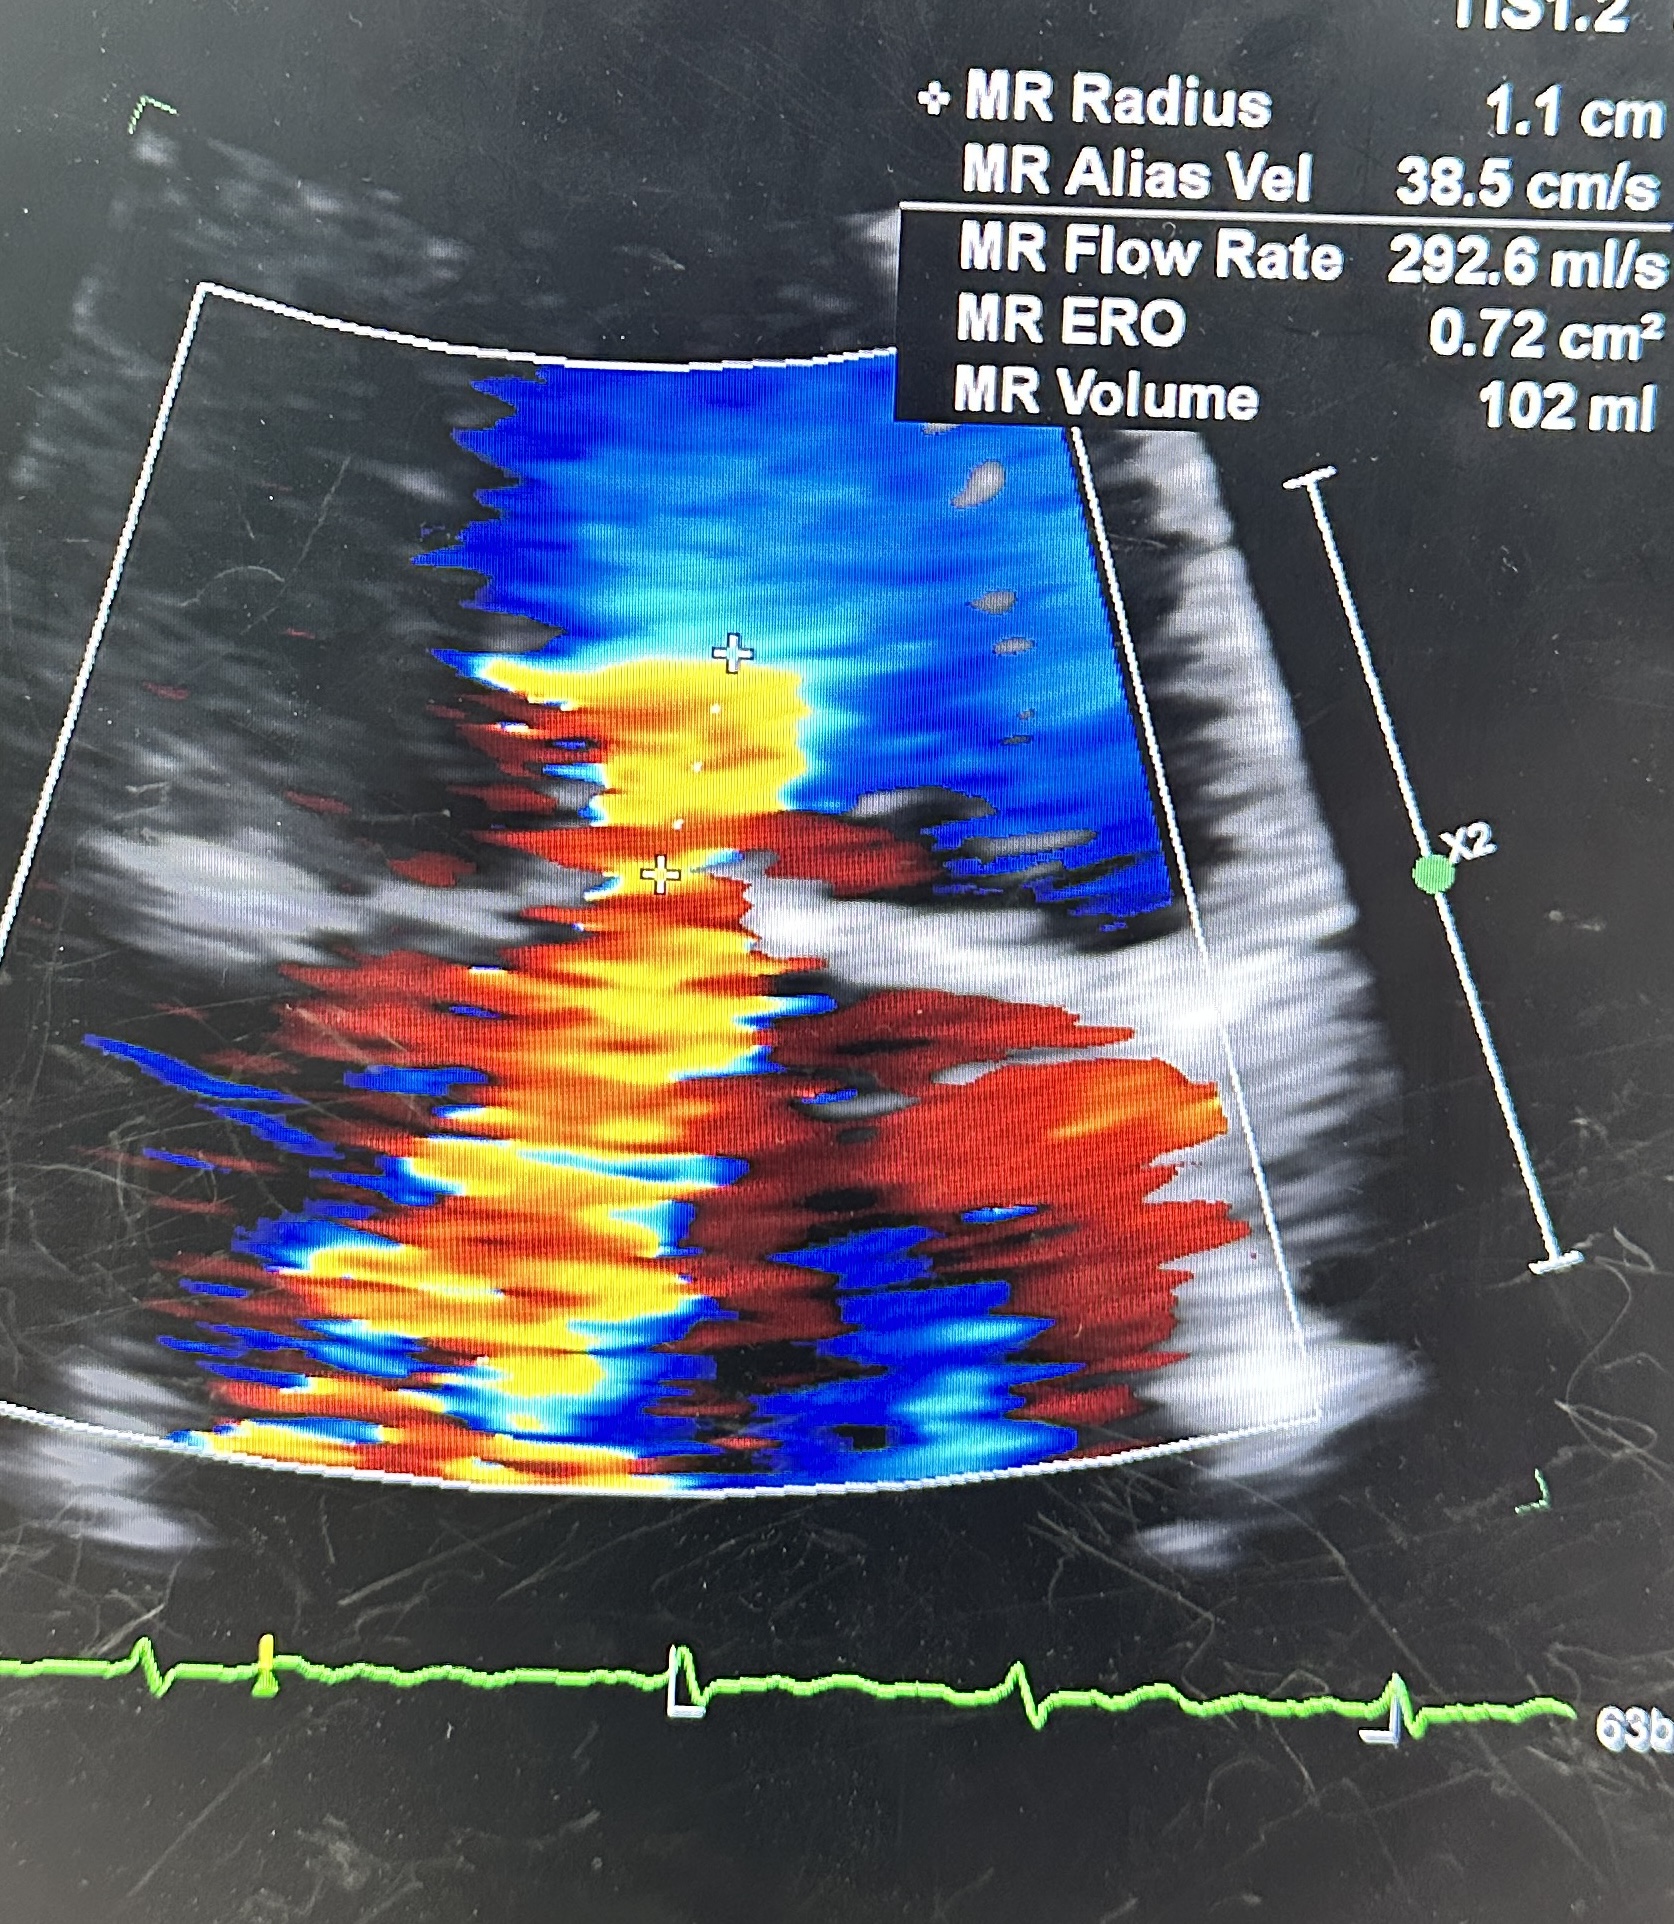

ECG: AF without acute ischemic change.CXR:CardiomegalyEchocardiogram: Severe primary (degenerative) mitral regurgitation due to mitral valve prolapses with flail P2 segment (Carpentier Type II), by integrative criteria (EROA ¡Ã0.4 cm©÷,regurgitant volume ¡Ã60 mL, vena contracta ¡Ã0.7 cm, systolic PV flow reversal,dense triangular CW jet). Baseline ECG: sinus rhythm without acuteischemic change.